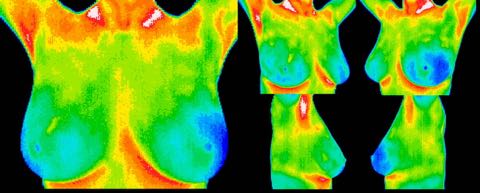

A complete normal study of the breasts